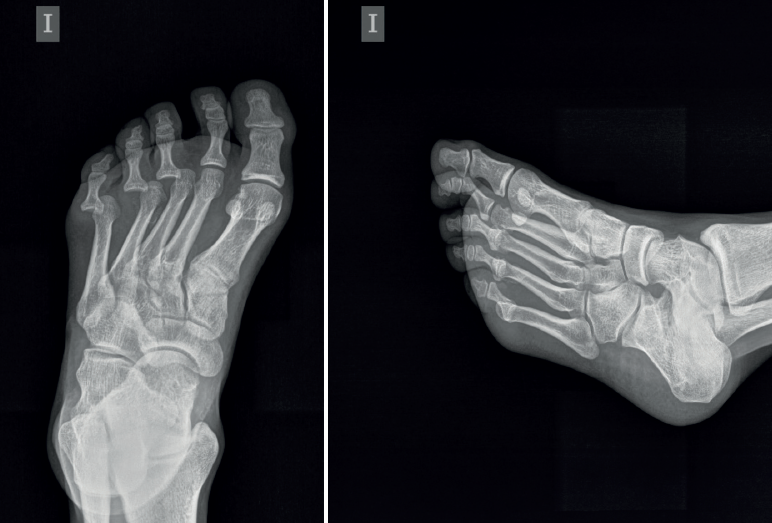

En el estudio radiográfico del pie se observó una luxación dorsolateral de la tercera a la quinta articulaciones metatarsofalángicas sin fracturas asociadas (Figura 1).